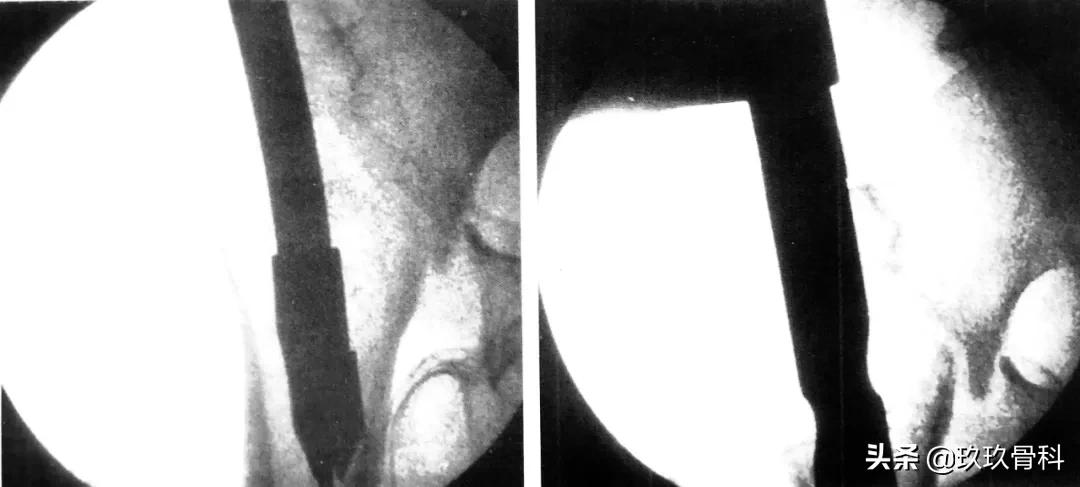

阶梯钻钻孔、正位拉力钉位置

侧位拉力钉位置、远端锁钉置入